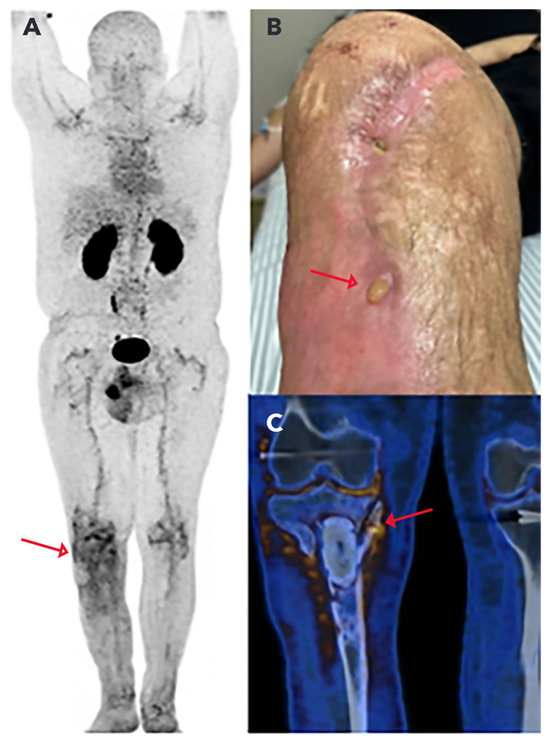

- Nogueira, S.A.; de Barboza, M.F.; Dell’Aquila, A.M.; Santos, D.C.B.; Osawa, A. Could 68Ga-DOTA-UBI-29-41 help identify chronic osteomyelitis on PET/CT images? A Pilot Study. Clin. Nucl. Med. 2023, 48, 982–984. [Google Scholar] [CrossRef] [PubMed]